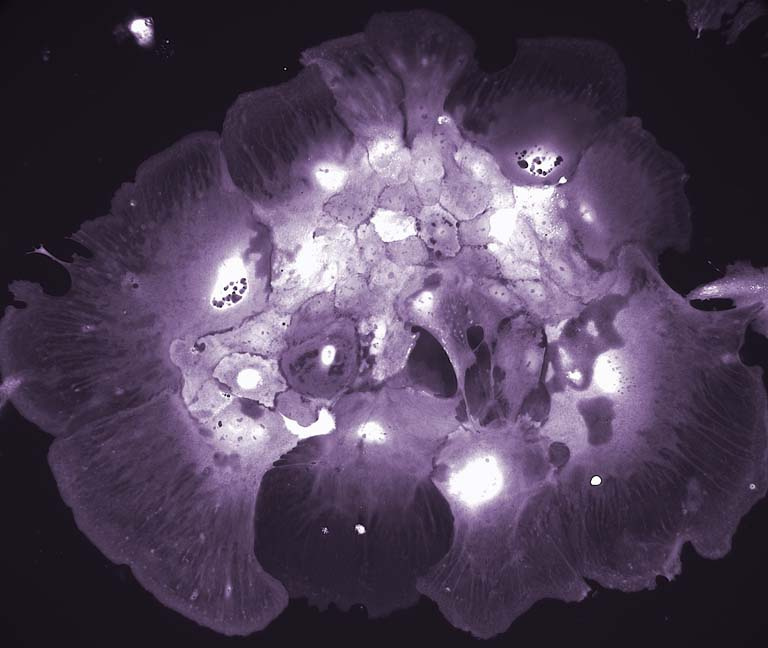

These images show cancer cells in the process of adapting to a new growth format, which will enable us to understand how cancer cells alter their metabolic behavior to survive in different environments. These images were of cancer cells that had been grown in 3D matrices previously and were transferred to a 2D growth format where they exhibit dramatic alterations and a high degree of variability, which we were documenting.

In this project we are trying to understand whether the growth format, nutrient conditions, or which mutations the cancer cells have is the most important variable for determining their metabolic behavior. These images are of one of the genotypes (APC-/- ; KRASG12D ; p53-/-) grown in a 2D format, and represents 1 of 32 conditions we are systematically profiling.